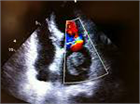

1. 心内血栓において重要なことは形成された血栓が血管を通して塞栓源となり種々の臓器に虚血性変化や梗塞を起こすことである(心原性塞栓症)。

1. 心内に血栓が形成されても、痛みや不快感などの自覚症状はまったく認めないので、起こり得る病態からみつけにくいことが重要である。頻度は7%程度との報告もある。